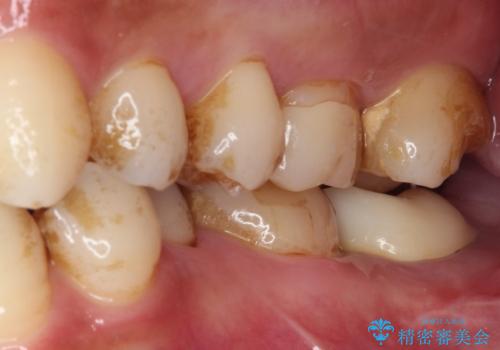

- かかりつけ医にて、歯の高さが不足しているためセラミッククラウンの装着はできないと言われたとのことで来院された患者様です。

診察したところ、確かに歯の高さは不足していましたが、土台の立て直しや歯の削り方を調整することでオールセラミッククラウンでも補綴可能と思われました。

ただし、クラウンの厚みは極力薄くした方が維持力が増すため、高強度のフルジルコニアクラウンにて補綴治療することとしました。

仮歯が途中外れることもなく、無事に補綴治療を行うことができました。

歯石や磨き残しなどが多いため、今後クリーニングを行っていきます。